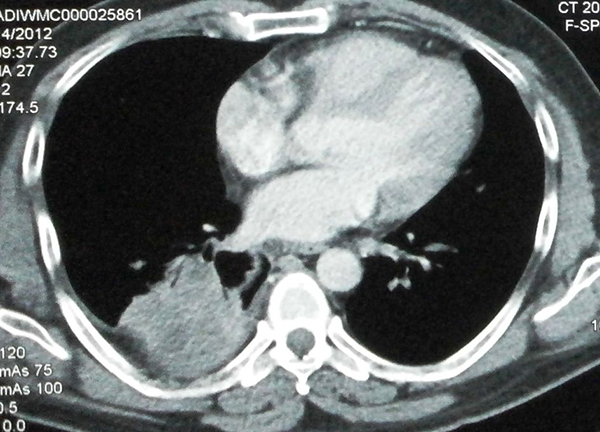

Clinical History: A 30-year-old woman presented with cough for two months and a single episode of minimal streaky hemoptysis. There was no history of recent weight loss or loss of appetite. A few days prior to presentation, she had minimal mucopurulent expectoration associated with dull aching right-sided chest pain. Physical examination revealed mildly reduced breath sounds in the right infrascapular area. Chest x-ray showed a heterogenous lesion in the right lower chest. Chest computed tomography (CT) scan showed a heterogeneous lung mass in the right lower lobe, which was regarded as suspicious for malignancy (Figure 1). Bronchoscopy showed a white membrane-like structure resembling a ruptured cyst within the airway (Figure 2). A biopsy of the membrane-like structure was performed (Figure 3).

Echinococcosis can involve any organ, but the liver and lungs are most commonly affected. The right lung is affected in 60% of cases, and 60% are in the lower lobes. The larvae of E. granulosus form cysts (“hydatid cysts”) in involved parenchymal organs. On pathologic examination, the wall of an intact hydatid cyst is composed of three layers. The outermost layer (pericyst, not seen in this case) is formed by the host reaction to the parasite. The next layer, also known as the ectocyst, is most commonly encountered in practice. It is characterized by a pathognomonic laminated membrane that has a pearly-white gross appearance and a lamellated microscopic appearance (Figure 3). The innermost layer, known as the endocyst or germinative layer, was not present in this case. It is composed of several tiny scolices/protoscolices, which contain rows of distinctive hooklets (Figure 4).

Clinically, patients with a hydatid cyst of the lung often remain asymptomatic until the cyst becomes very large, causing symptoms due to compression of adjoining structures or rupture. Cyst rupture is the most common complication. In most cases, the diagnosis of echinococcosis is established by imaging and serology. However in cases of cyst rupture, imaging may be misleading, as in the present case. The sensitivity of serology for pulmonary hydatid cysts is low (60%) and there are also many false positives. The specificity increases when the arc 5 test is used instead of ELISA or indirect hemagglutination. In cases with atypical imaging or negative serology, pathologic examination is required for a definitive diagnosis.